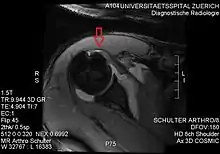

Imaging

There is no singularly imaging device or technique for a satisfying and complete subscapularis examination, but rather the combination of the sagittal oblique MRI / short-axis US and axial MRI / long-axis US planes seems to generate useful results. Additionally, lesser tuberosity bony changes have been associated with subscapularis tendon tears. Findings with cysts seem to be more specific and combined findings with cortical irregularities more sensitive.[5]

Since the long biceps tendon absents itself from the shoulder joint through the rotator cuff interval, it is easily possible to distinguish between the supraspinatus and the subscapularis tendon. Those two tendons build the interval sling.

In comparison to a checking MR Arthrography Strobel K. et al. has arrived at the conclusion that through THI it is possible to achieve a generally improved visibility of joint and tendon surfaces, especially superior for subscapularis tendon abnormalities.[9]